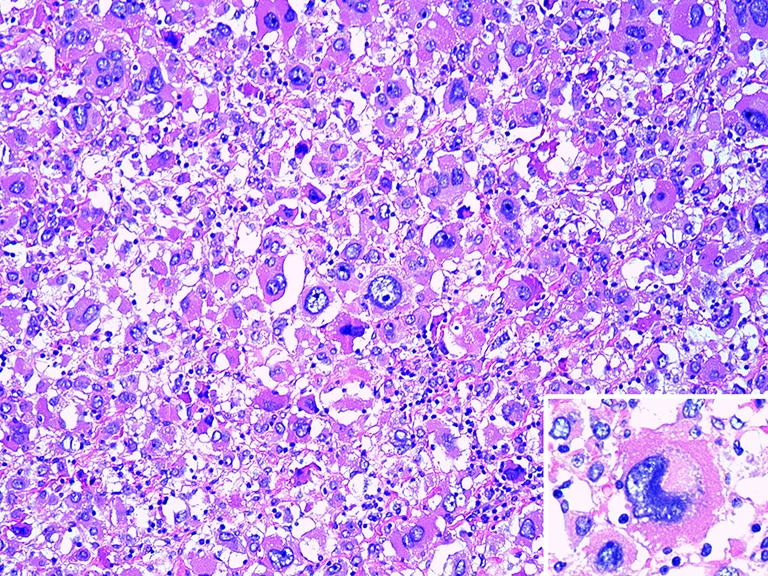

Fig. 1.

Two areas from a pediatric adrenal cortical neoplasm, weighing 88 g. Large, multinucleated tumor giant cells, with hyperchromatic nuclei and nuclear pseudoinclusions in a few, among smaller tumor cells displaying high nuclear/cytoplasmic ratio and hyperchromatic nuclei (a). Tumor cells with moderately atypical nuclei and an atypical mitotic figure near the center of the field (b). Despite these worrisome histological features, this neoplasm had a benign biological behavior